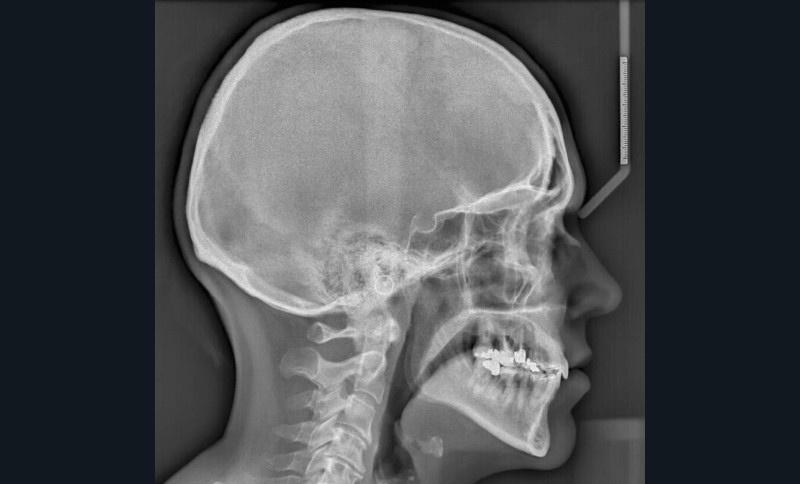

L’examen radiographique (fig. 3-5) nous indique une Classe I squelettique de Ballard (ANB 0°) sur un schéma facial à tendance hyperdivergent (FMA 28°). L’analyse céphalométrique confirme la vestibulo-version incisive (I/SN 111° ; IMPA 94°). La lyse osseuse est généralisée.